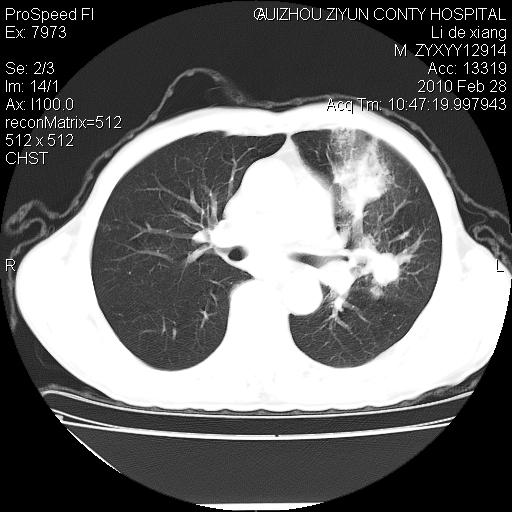

标题: CT24776:男 71Y 咳嗽咳痰胸痛两月,伴声音嘶哑。 [打印本页]

左侧中央型肺癌伴左肺上叶阻塞性肺炎及节段性不张可能性大,建议纤支镜检查!

左侧中央型肺癌伴左肺上叶阻塞性肺炎及节段性不张可能性大,建议纤支镜检查!纵隔淋巴结转移.

左肺门部肿块,伴左上肺斑块影,周边模糊,支持左肺中央型肺癌伴节段性不张及阻塞性肺炎,结合支气管镜检查。

左上叶支气管狭窄,阻塞性病变,肺门肿块,纵隔及肺门淋巴结增大,中央性肺癌

左肺中央型肺癌并阻塞性改变、纵膈 淋巴结转移